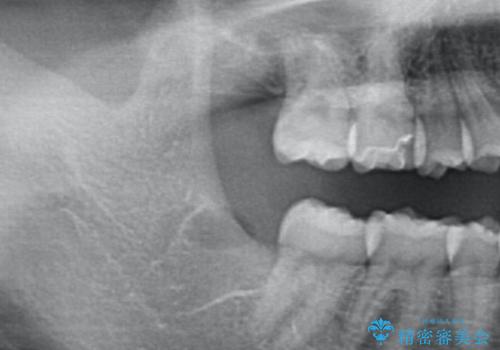

歯の高さを出すための親知らず抜歯と歯肉切除

担当医 岡田康成